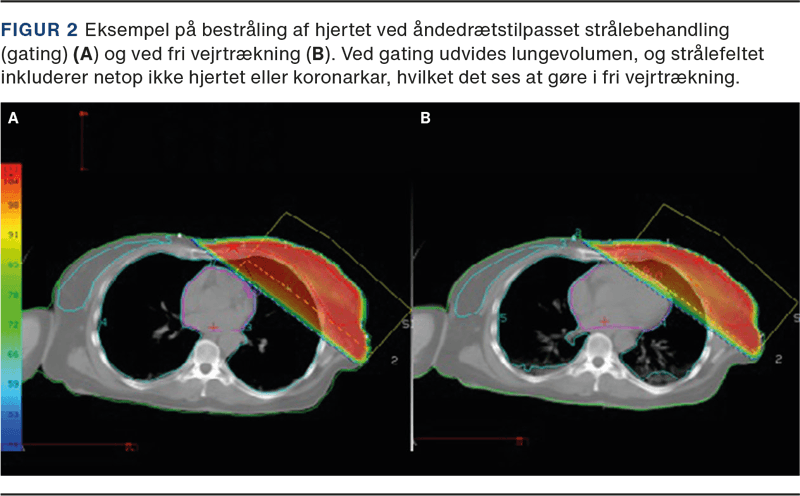

PBI tilbydes patienter med lavrisikobrystkræft, idet lokalt tilbagefald oftest findes inden for den samme kvadrant af brystet, som den oprindelige tumor var lokaliseret i. Ved PBI bestråles kun et begrænset volumen af brystet svarende til området omkring det oprindelige tumorleje (se Figur 1). Dette giver mindre fibrose samt en lavere risiko for senfølger på grund af en reduktion i hjerte- og lungedosis. PBI blev indført i Danmark i 2016 på baggrund af resultaterne fra DBCG’s PBI-studie [7] og det engelske IMPORT LOW [8]. I de to studier blev PBI ikke fundet dårligere end WBI og med en generelt meget lav forekomst af lokalrecidiv. Da der ikke er fundet signifikant højere risiko for tilbagefald ved PBI, taler hensynet til et bedre kosmetisk resultat og lavere risiko for senfølger for anbefaling af PBI hos lavrisikopatienter.

For de få patienter, hvor den planlagte dosis til hjerte og lunger overskrider de anbefalede dosisgrænser, kan brug af moderne planlægning med rotationsteknik være en mulighed. Her omfordeles stråledosis, således at der sikres en mere konform dosisfordeling i højdosisområdet, men til gengæld eksponeres et større volumen af modsatte bryst og lunge, som ellers ikke ville være medbestrålet, for lav dosis (se Figur 3). En anden mulighed er protonbehandling, hvor de anderledes fysiske egenskaber ved protoner potentielt kan forbedre dosisfordelingen. Protonbehandling anses for eksperimentel ved strålebehandling af brystkræft, hvorfor DBCG’s SKAGEN II-studie tilbyder randomisering mellem standardfotonbehandling og protonbehandling til patienter, hvor stråledosis til hjerte og/eller lunger overskrider de anbefalede dosisniveauer.